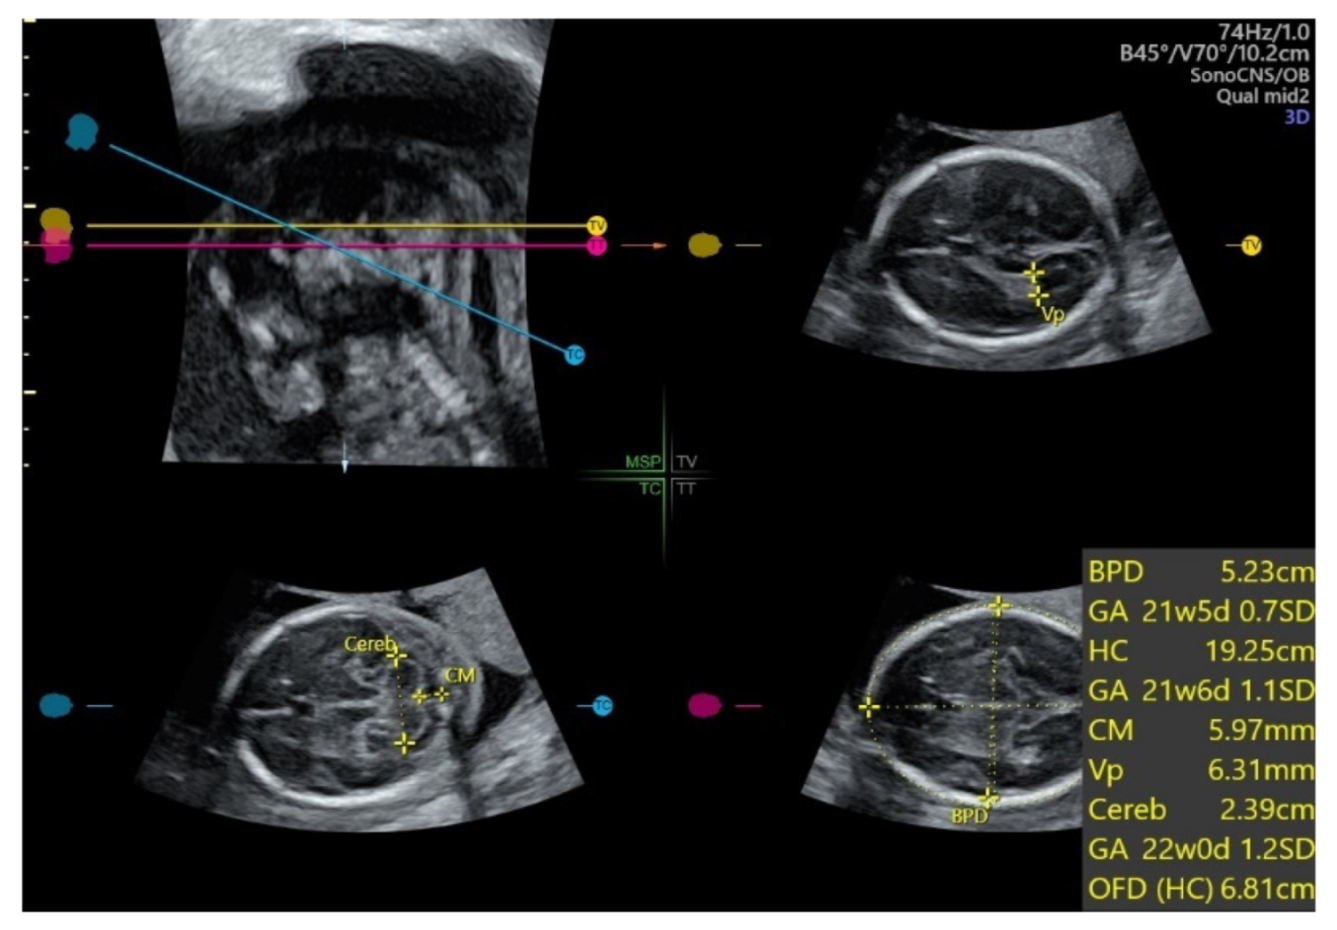

With automatic image recognition technology applied on an acquired 3D ultrasound volume of the fetal head from the BPD plane, SonoCNS allows auto measurement of fetal biometry including BPD, HC, atrium of the posterior horn of the lateral ventricle (Vp), transcerebellar diameter (TCD), and cisterna magnum (CM) [70] (Figure 14). A recent study showed that this 3D automated technology reliably identified and measured BPD and HC but was less so for TCD, CM, and Vp [70]. Further optimization of this automated technology is required.

Figure 14.

SonoCNS, after volume acquisition of the fetal brain at biparietal diameter plane at 21 weeks gestation, showing auto measurement of biparietal diameter (BPD), head circumference (HC), atrium of the posterior horn of the lateral ventricle (Vp), transcerebellar diameter (TCD), and cisterna magnum (CM).